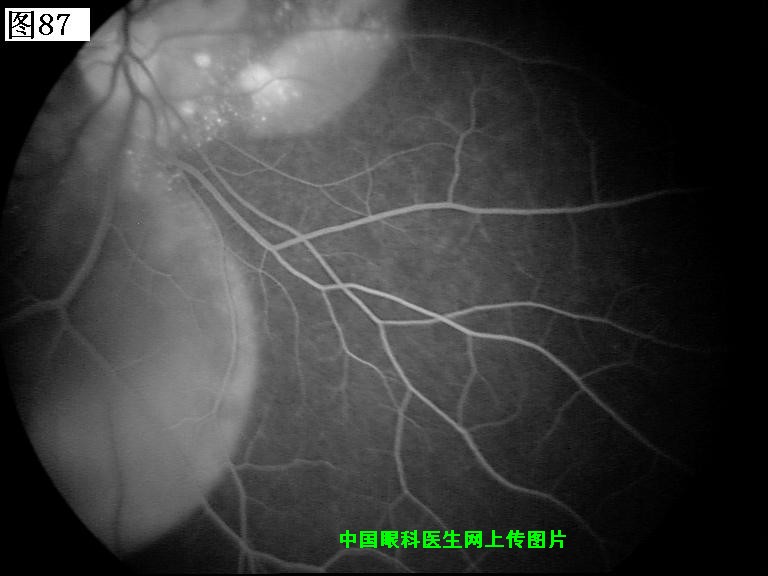

优秀眼底图片奖应征作品展示

85 86 87 88